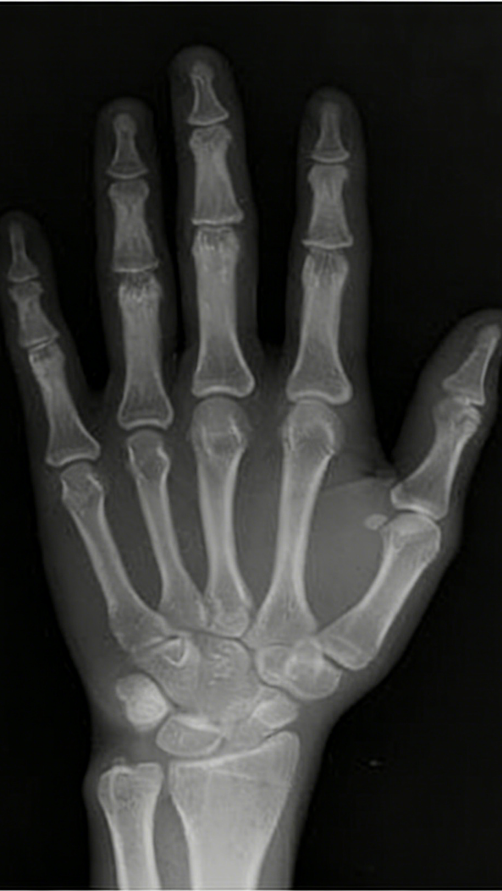

核心标准:骨龄检测,拍左手腕骨X光片查看骨骺状态